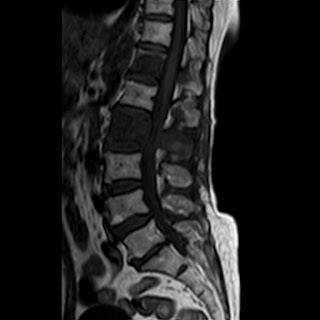

Needed help for this currently admitted 60 years old woman with gradual paralysis and severe back pain for the last few weeks. On examination there was slight gibbus and absent lower limb reflexes and MRI shows a lesion at L3 as well as T3.

Radiological images:

HRCT is also done on 13/11/15